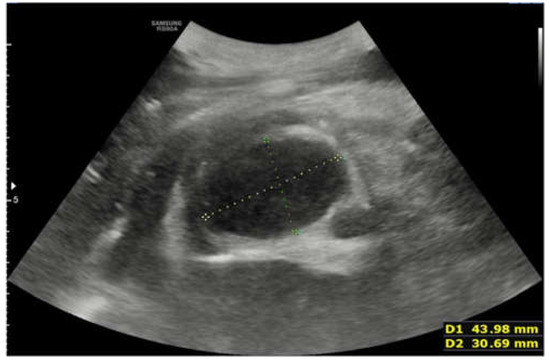

2. Case Report